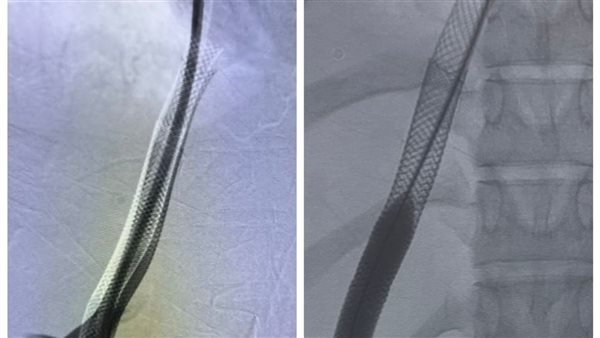

قام الفريق الطبي بإجراء عملية دقيقة لتركيب دعامات معدنية بين الوريد الأجوف السفلي والوريد البابي الكبدي باستخدام تقنية الـ (TIPSS)، والتي تُعد خياراً علاجياً متقدماً ينفرد به مستشفى الراجحي كونه المركز الوحيد في صعيد مصر الذي يقدم هذه التقنية التي تتطلب مهارة ودقة فائقة وتجهيزات طبية خاصة.